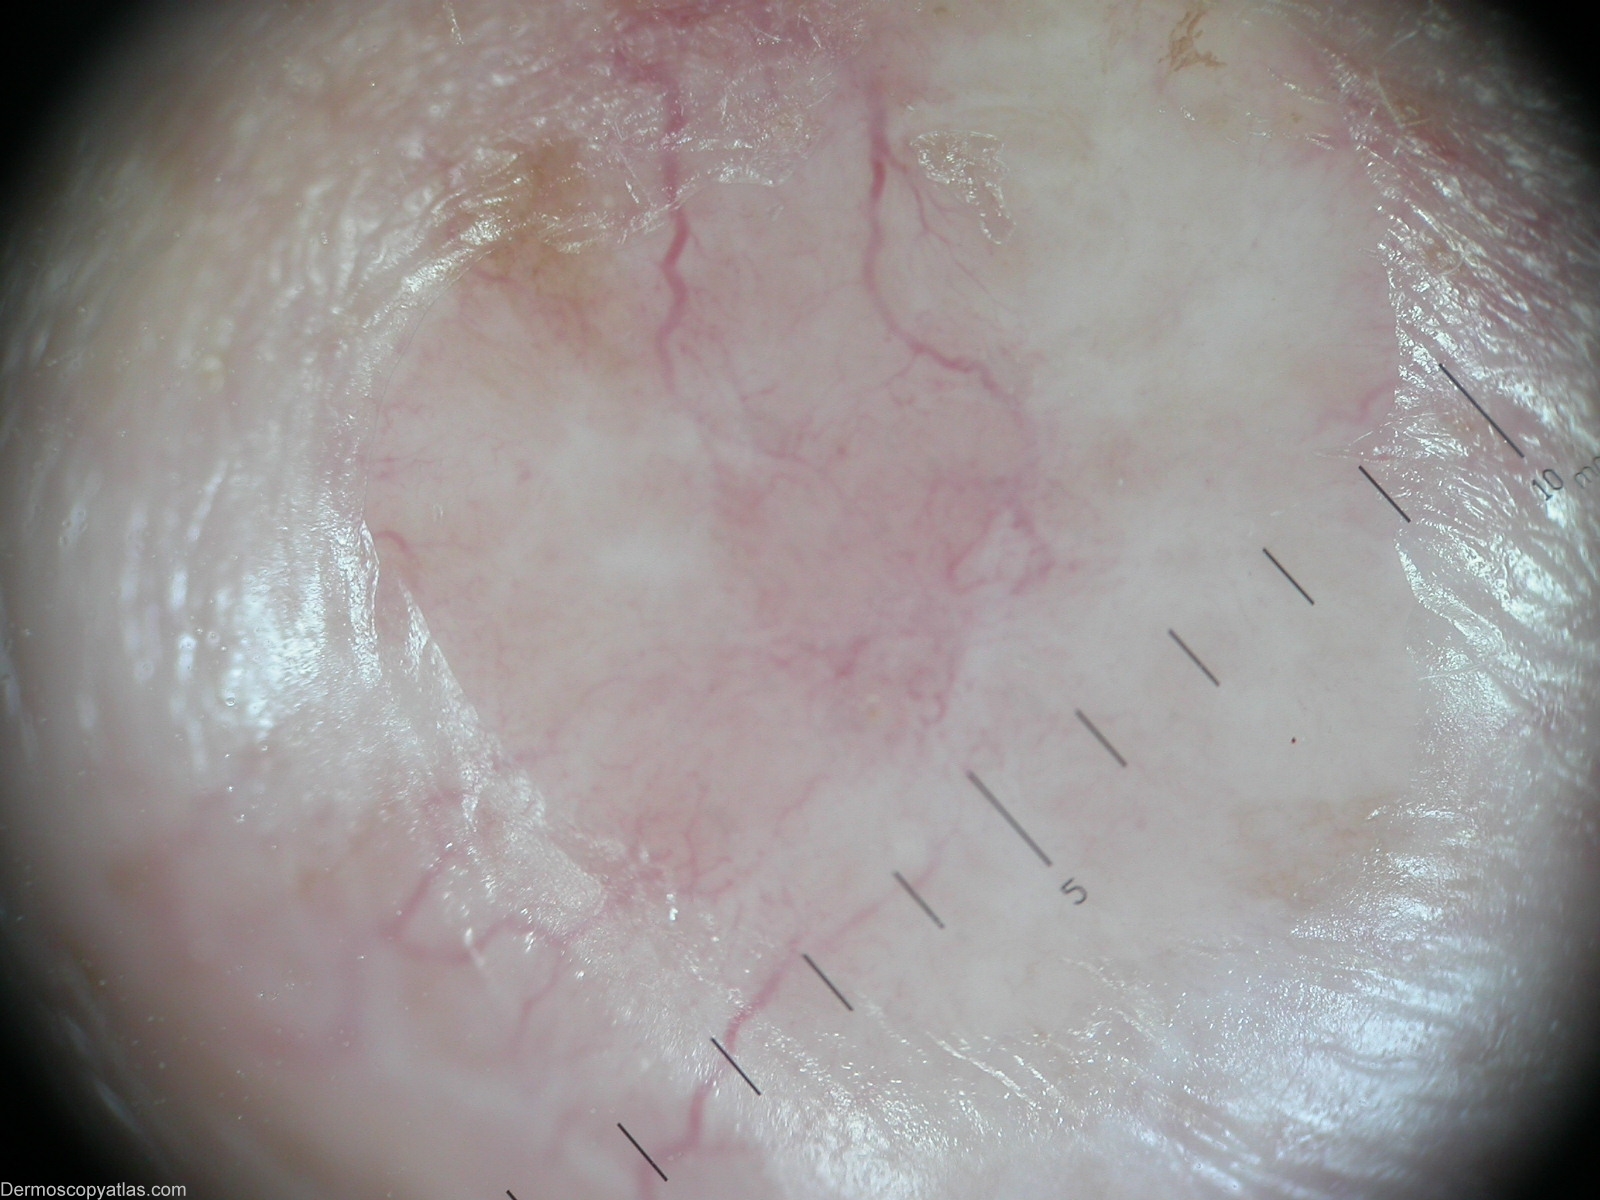

Image Number #2438 (BCC morphoeic)

Site: Cheek

Diagnosis: BCC morphoeic

Description: Arborizing vessels

This 76-year-old man was evaluated for an enlarging nodule with telangiectasia in periphery of the lesion on his chest for over a year. A skin biopsy demonstrated a BCC morpfoeic.

Dermoscopic description:Arborizing vessels.